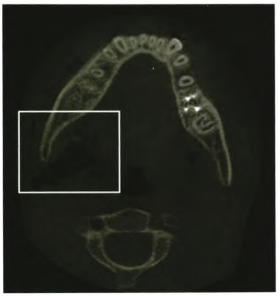

【辅助检查】

临床检查可见右下第一恒磨牙远中牙合面深大龋洞(见图1),可探及露髓孔,叩痛(±),患牙无松动,牙龈无异常,牙髓冷测试敏感。根尖x线片示根尖孔闭合,根尖周未见低密度影及根周膜增宽,未见根尖弯曲。